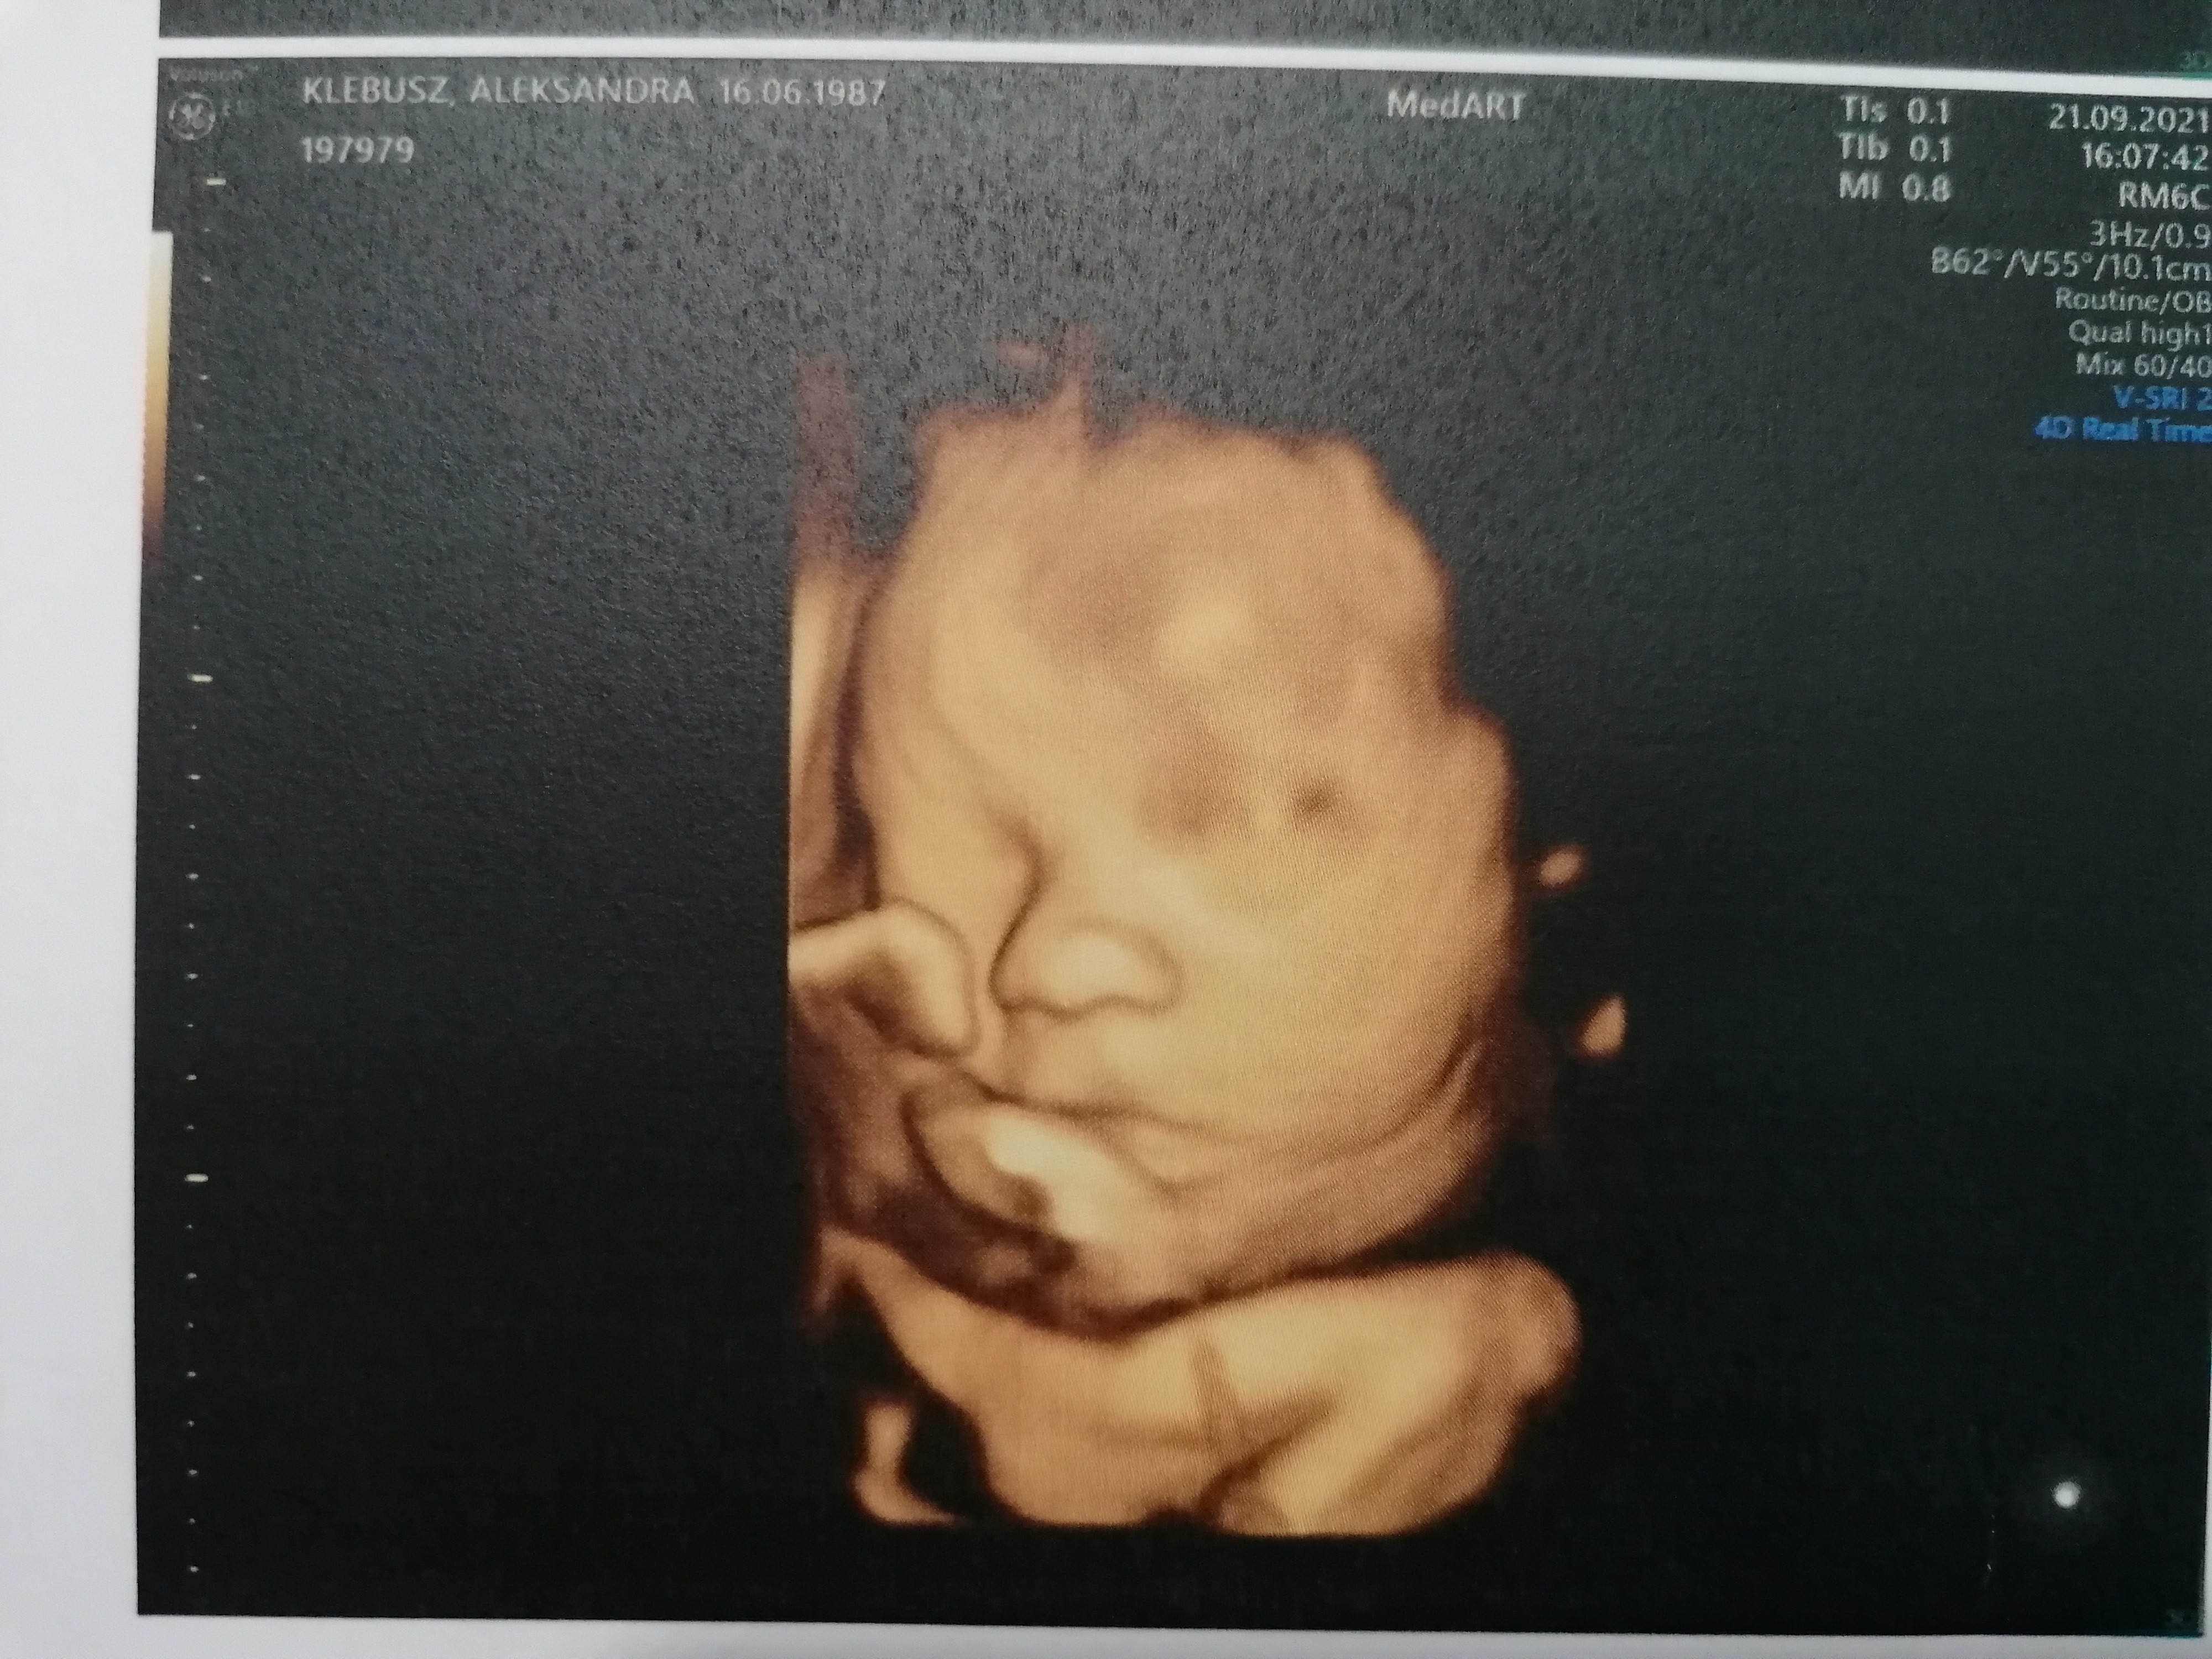

Jestem po wczorajszej wizycie, usg 30 tygodnia. Mała waży 1590g i rozwija się zdrowo :) co mnie bardzo ucieszyło szyjka przestała się skracac!

I udało się nawet zrobić zdjęcie :)